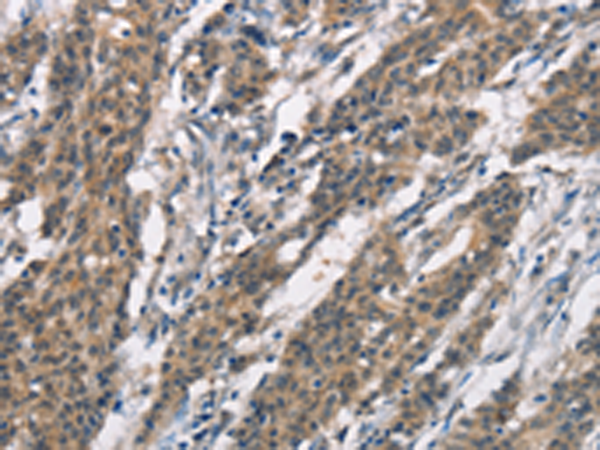

分类: 科研抗体货号: P11573别名: HYDM; PAN7; NALP7; NOD12; PYPAF3; CLR19.4应用: IHC反应种属: Human